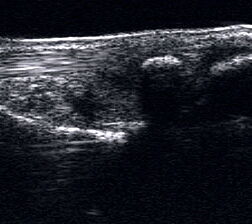

Tendopathie der Achillessehne

Lagerung: Bauchlage, ggf. Sprunggelenk mittels Rolle unterlagert.

Schnittführung: LS und TS über der Achillessehne in leichter manueller Vorspannung der Achillessehne.

Referenzstruktur: Direkt unter der Haut und der dünnen Subkutis liegt echogen und straff parallel die Achillessehne mit ihrem echogenen Peritendineum.

Befunde: Klassischerweise findet sich eine normal echogene spindelförmige Verdickung einige Zentimeter über der Insertion (Abb. 60). In der Frühphase zeigen Tendinopathien eine echoarme Verdickung. Im Verlauf finden sich zunehmend echogenere Bezirke und Inhomogenitäten, teilweise mit Einziehungen und rau erscheinendem Peritendineum. Ist die Sehne teilweise nicht mehr abgrenzbar, kann bereits ein Übergang in eine teilweise Kontinuitätsauflösung vorliegen. Ein peritendinöser Randsaum ist vor allem in frühen Phasen zu beobachten. Flüssigkeitsareale, die von der echogenen Sehne abgrenzbar sind, sprechen jedoch auch an der Achillessehne für eine Rissbildung. Auch Kalkeinschlüsse oder peritendinöse Verkalkung mit Schallschatten sowie intratendinöse Zysten werden beobachtet.